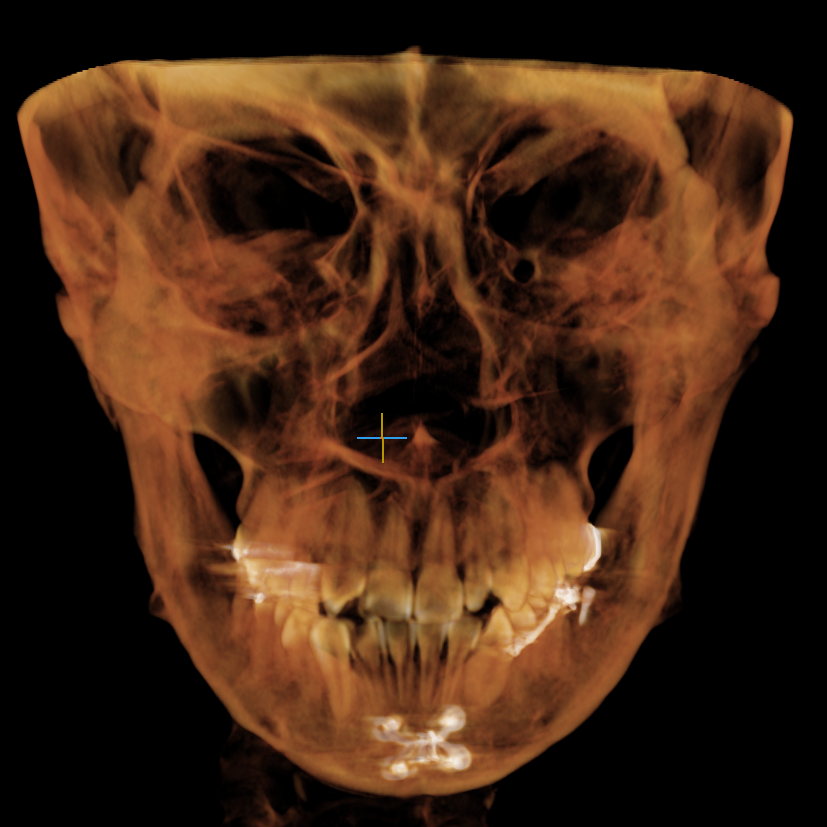

저는 10년 넘게 전에 윤곽 수술을 했고,윤곽 수술후  그동안은 별 문제 없었는데, 최근 들어 턱 쪽이 시리거나 찌릿한 통증, 또 치아까지 자극되는 느낌이 있어서 신경이 쓰이더라고요. 처음엔 그냥 피로감인 줄 알았는데 점점 자주 느껴져서 결국 핀제거를 결심했어요.

상담 때부터 김도원 원장님이 너무 믿음직스러웠어요. 제 예전 수술 이력과 핀 위치를 CT로 하나하나 확인해주시면서 왜 이런 증상이 생기는지, 제거 시 주의할 점은 무엇인지 꼼꼼하게 설명해주셨거든요. 사실 오랜된 핀제거라 걱정도 많았는데, 김도원 원장님이 안전하게 가능하다 는 말을 해주셔서 용기 냈어요.